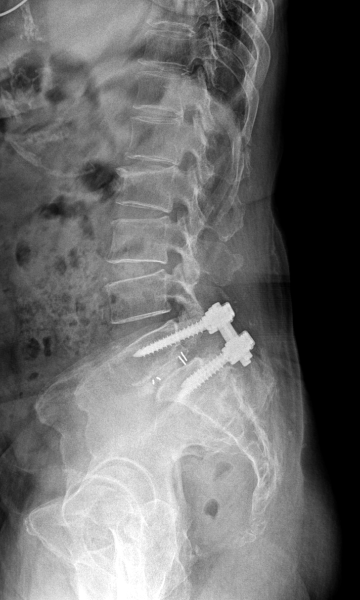

다리 저림이 심하고 보행이 힘든 경우 수술적 치료가 필요하며 척추고정술을 통해 신경 압박을 풀어줍니다.

척추전방전위증 수술 전·후

2022.09.21

2022.12.30

ㆍ환자 동의를 받은 자료이며, 이미지 사진은 실물과 다를 수 있습니다.